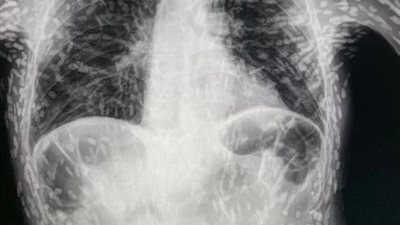

هل تعرض الثدي للأشعة السينية آمن؟

هل يؤثر فصل الشتاء على دقة تصوير الثدي بالأشعة السينية؟

دراسة: تصوير الثدي بالأشعة السينية الإيجابية الكاذبة يرتبط بزيادة خطر الإصابة بالسرطان

بالتزامن مع شهر التوعية بسرطان الثدي.. تعرف على أهمية الكشف المبكر